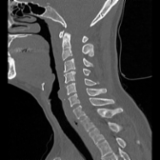

The severe cervical spine pain prompted an emergency MRI examination, which showed a clear prevertebral inflammatory soft tissue process. On close inspection, a calcific deposit anterior to the dens axis can already be suspected on MRI (especially T2 or axial T1fs Gd+). The calcium depot is only shown very fluffy on X-ray and CT, suggesting an acute stage with precipitation/resorption of the calcific milk.

Therapy is initially conservative. Punctures and surgery of the calcific deposit can be done from endooral.